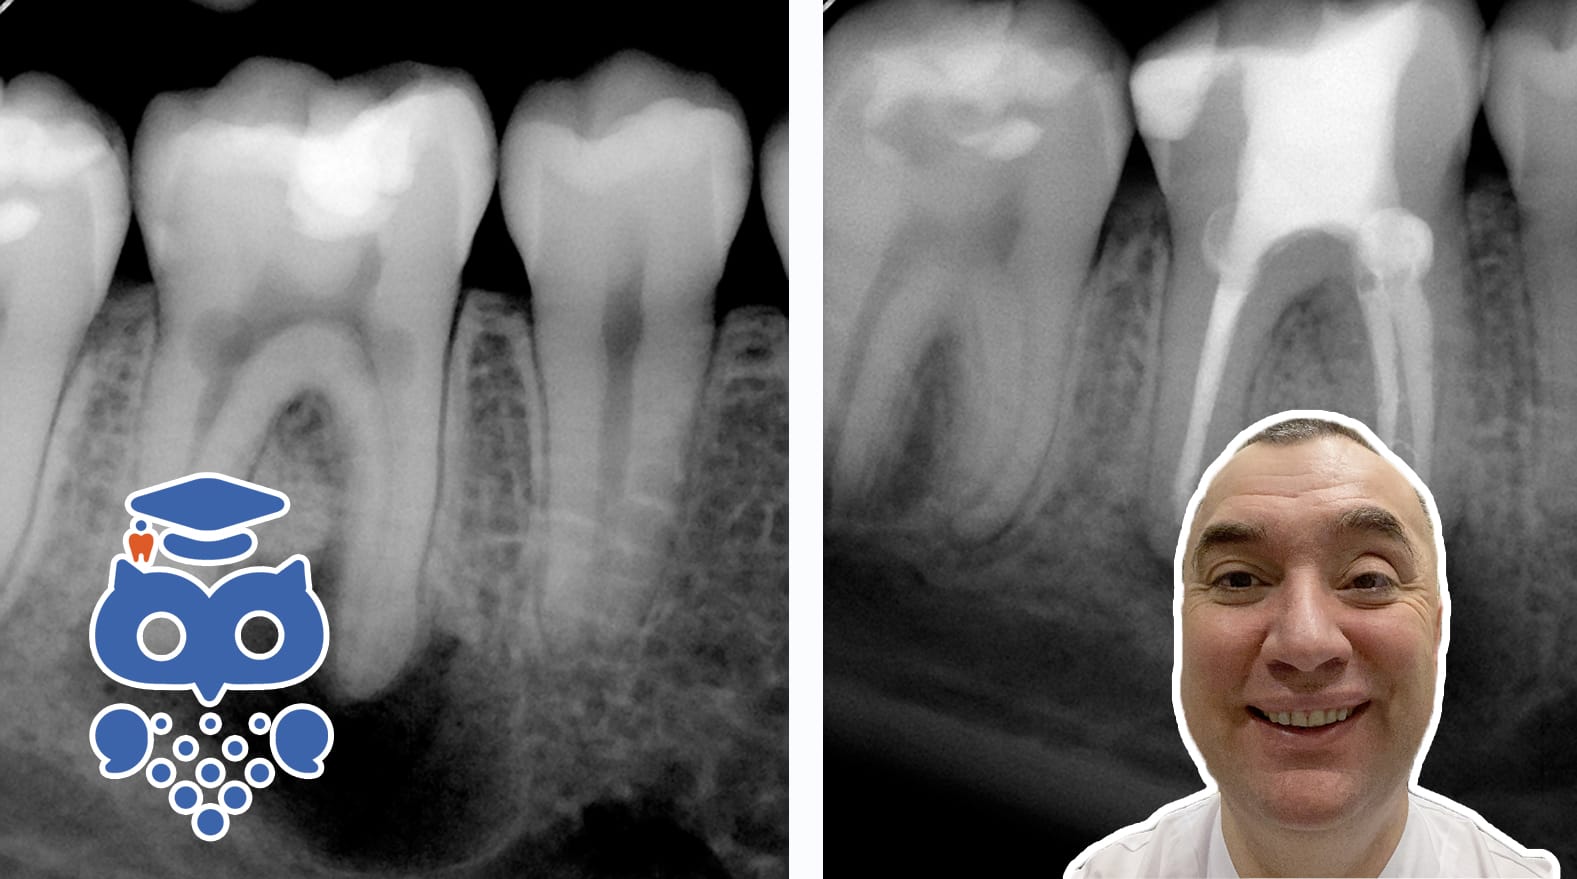

Rotresorption – extern

Normalt skyddar rothinnan och rotcementet tanden från resorption. Skador efter trauma kan dock leda till olika typer av rotresorption: ytresorption, som oftast självläker; infektionsrelaterad resorption, som kräver snabb endodontisk behandling; och ersättningsresorption (ankylos).

När skador uppstår på rothinnan efter trauma (tandluxationer och exartikulationer) kan olika typer av rotresorption uppkomma:

Rotresorptioner